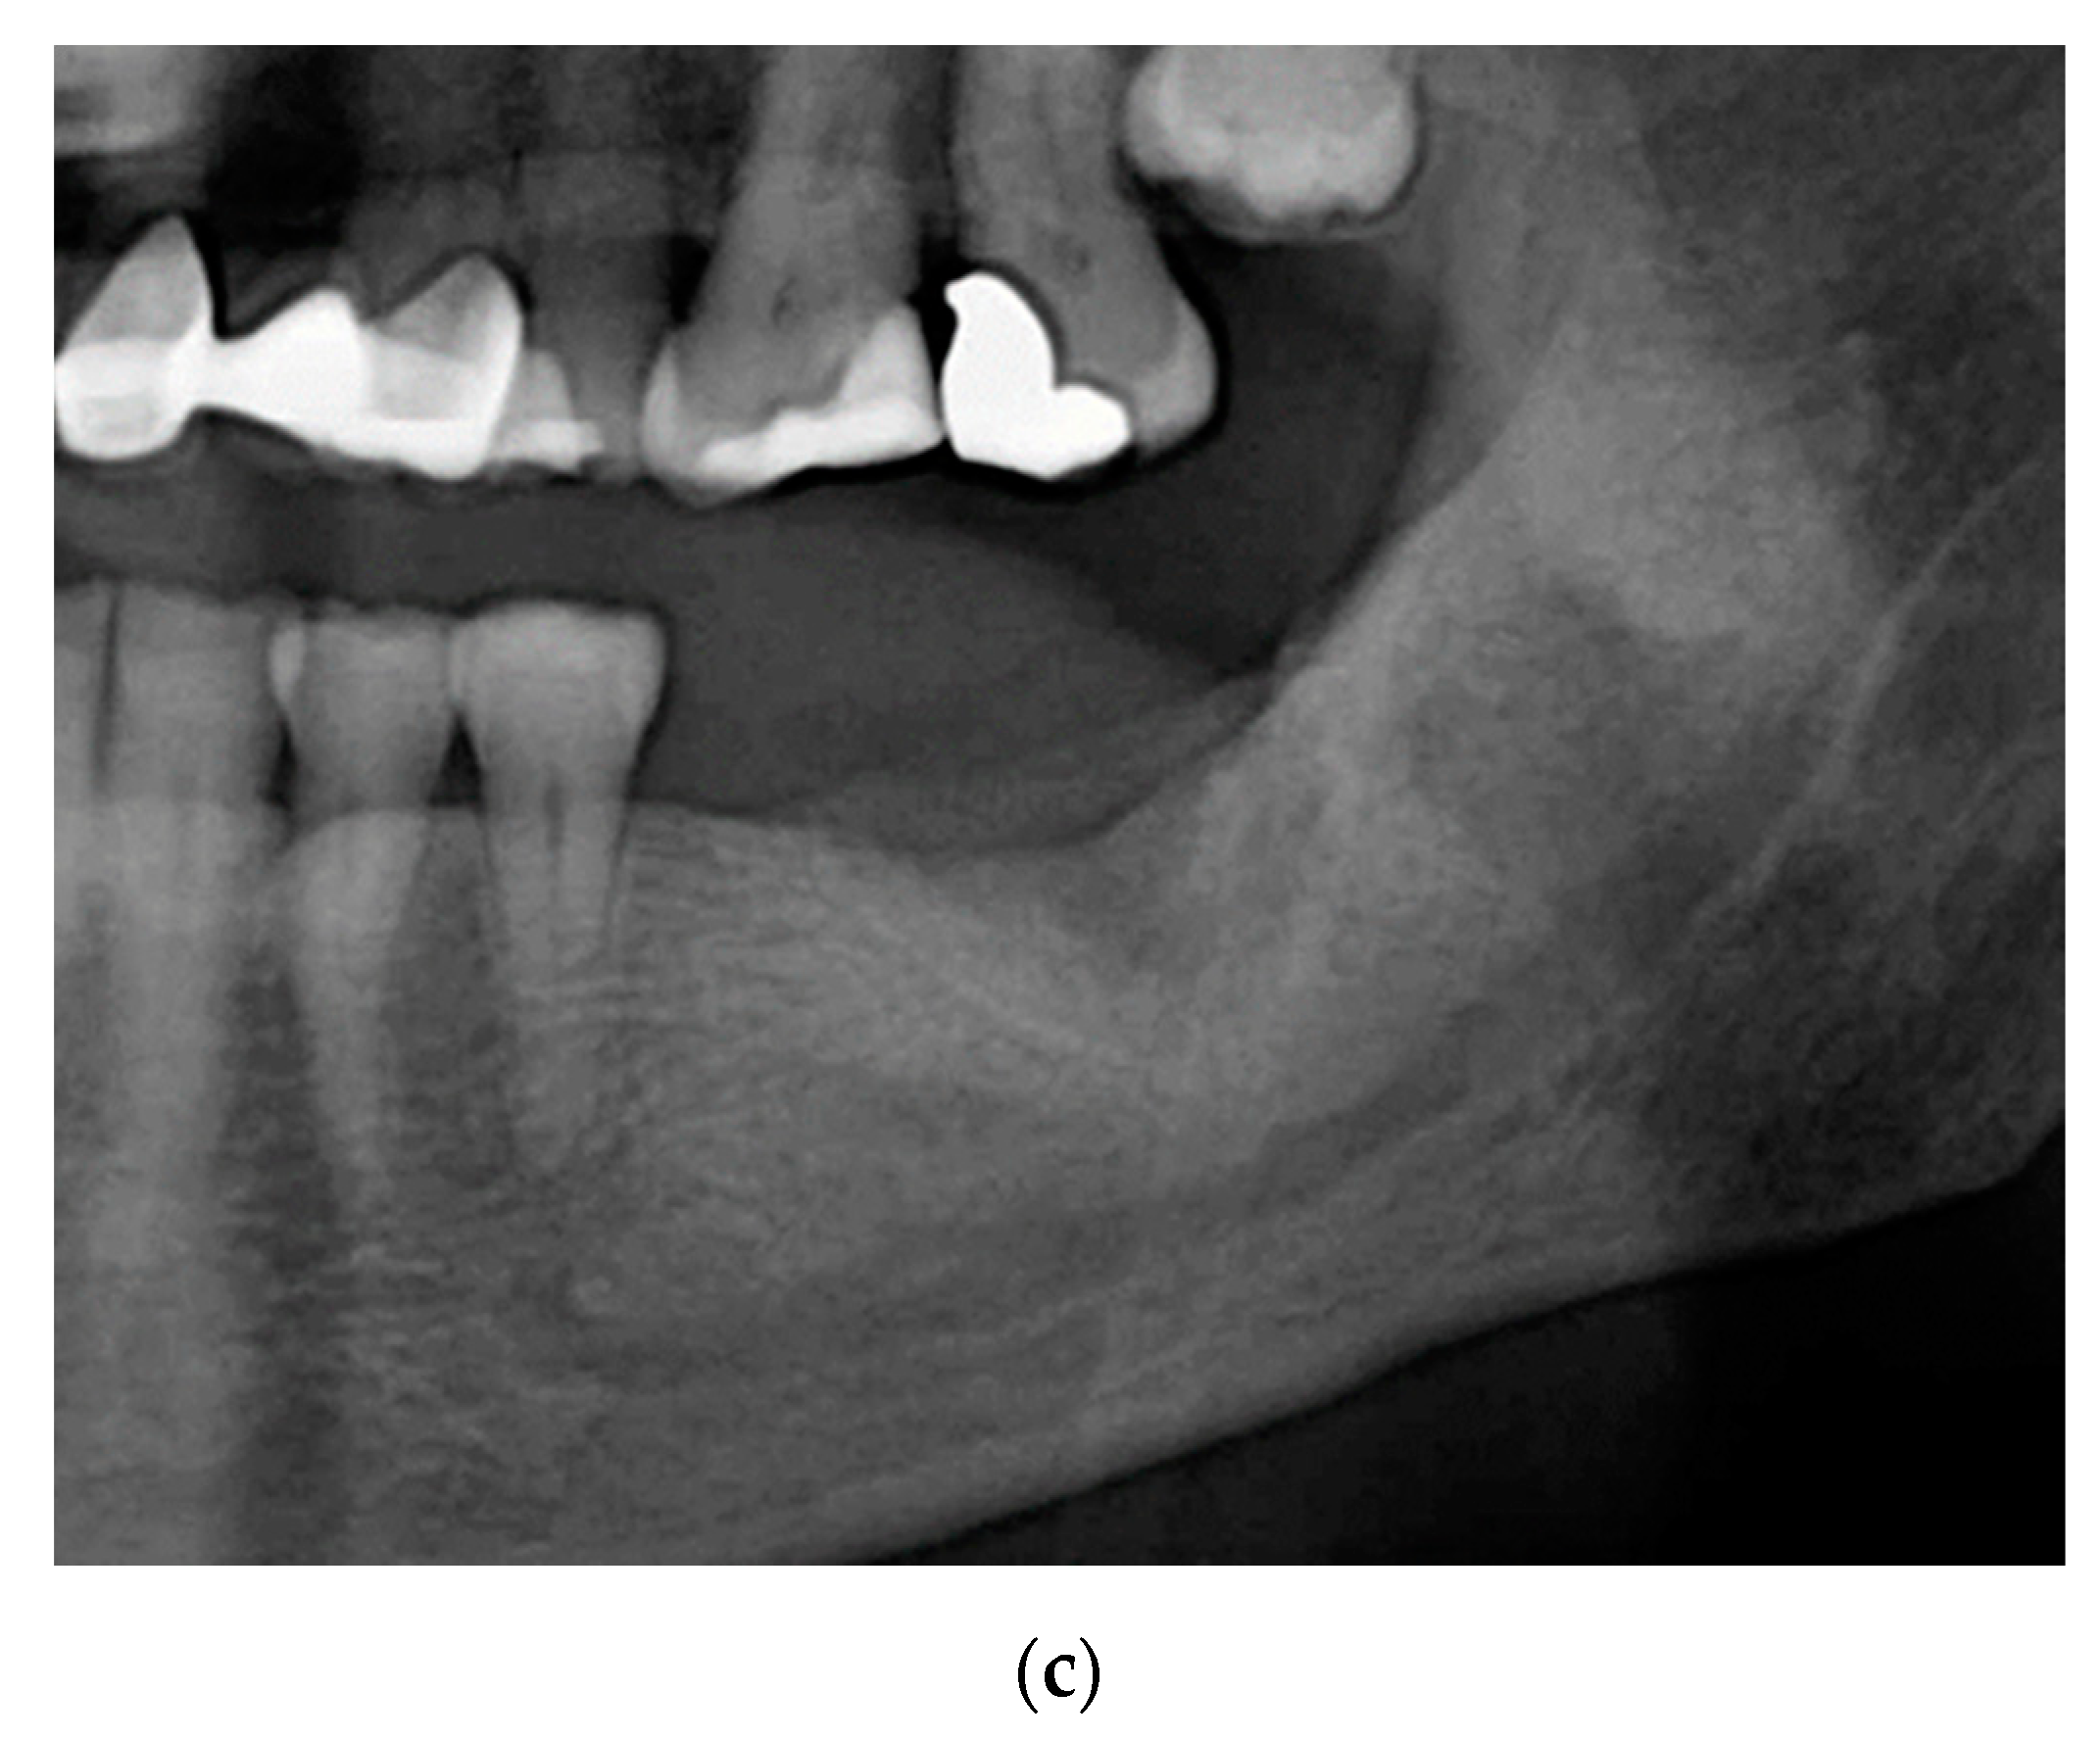

2.3. Case 3: Conservative Treatment + SURGERY + PRF-L

3. Results